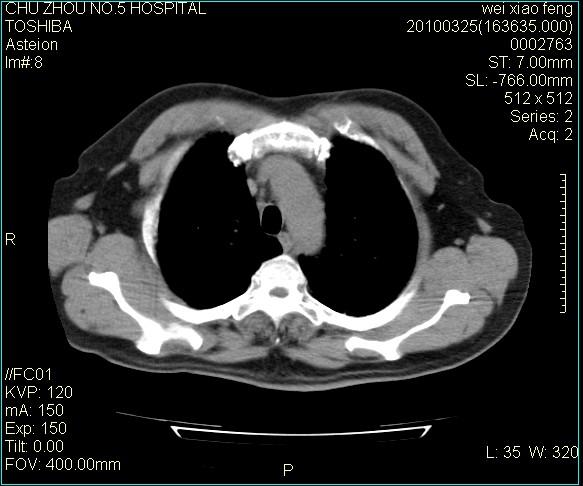

男,60岁,反复咳、痰、喘3月,加重3天。

双肺间质性改变。

考虑双肺血型潘散肺结核/

间质性肺炎伴间质纤维化!不排除伴有职业病!

急性血型潘散肺结核。

双肺间质纤维化,双肺血型潘散肺结核。

考虑间质性肺炎伴间质纤维化。

右肺中叶结节影为原发灶,考虑右肺中叶周围型肺癌并淋巴道转移